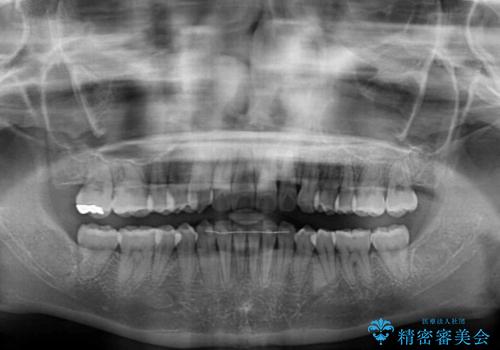

- 前歯のデコボコと強い咬みしめを気にして来院された患者様です。

インビザラインを用いて、前歯の叢生を解消するとともに、ディープバイトを改善していくこととしました。

海外へ転居する予定があったため、1日22時間以上の装着時間をしっかりと守っていただき、予定期間よりも早く、思っていた以上にきれいに仕上げることができました。